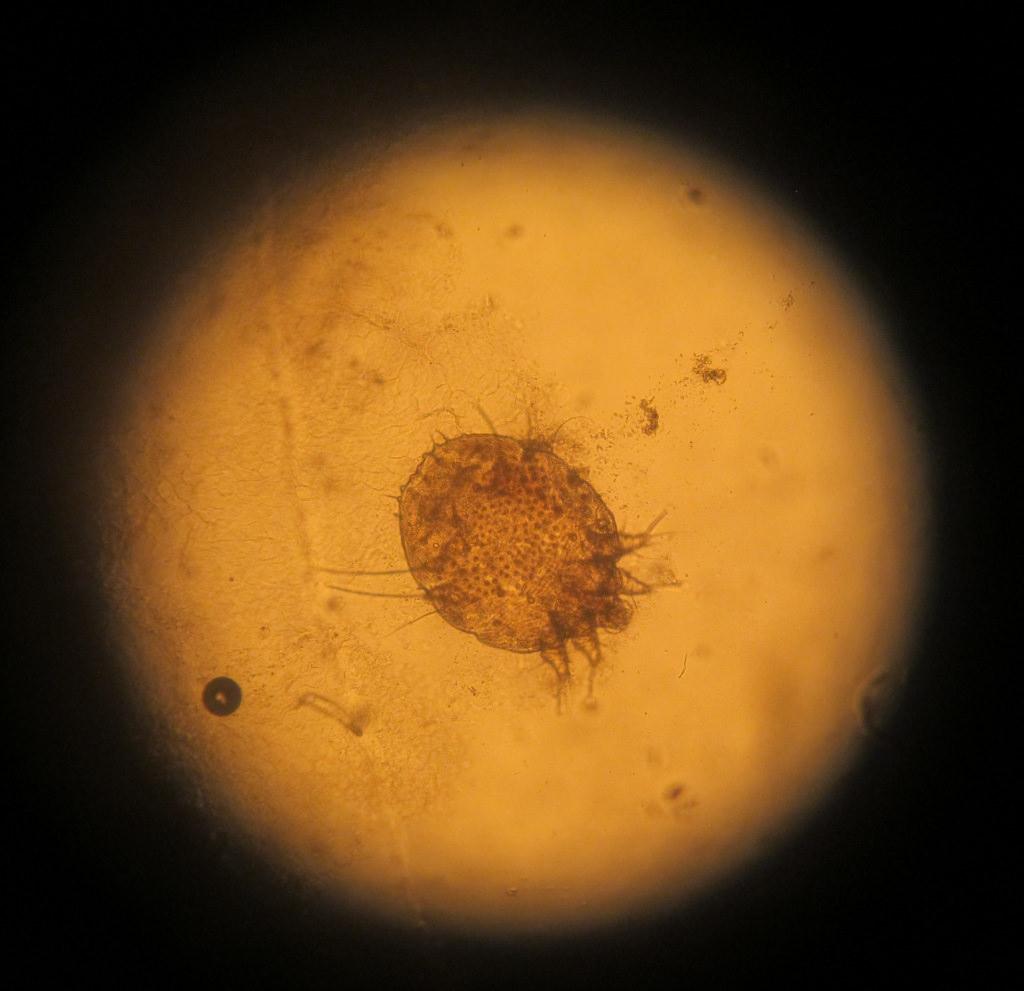

как выглядит чесоточный клещ

Заражение осуществляют самки и личинки. Самка обитает в коже. В дневное время она неактивна, но вечером она активно прогрызает ходы, размножается, питается и выделяет продукты переработки. Следовательно, самый большой риск заразиться появляется именно в вечернее-ночное время, когда клещ проявляет большую активность.